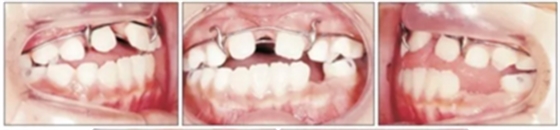

第二階段(圖5,6;表2)

面弓矯治包括在混合牙列及早期恒牙列的傳統(tǒng)牙支抗面弓及恒牙列的骨支抗面弓。由于患者曾行腭成形術,為了將矯治力傳遞到上頜骨,使用唇舌弓而不是快擴。8歲5月時開始用面弓聯(lián)合唇舌弓矯治(500g/邊,與合平面呈30°向下),持續(xù)3年6月?;颊吲宕鲿r間為12-14時/天。